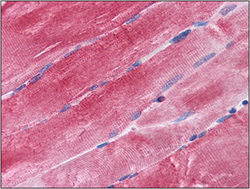

AP23023PU-N IHC

Full details

Method: